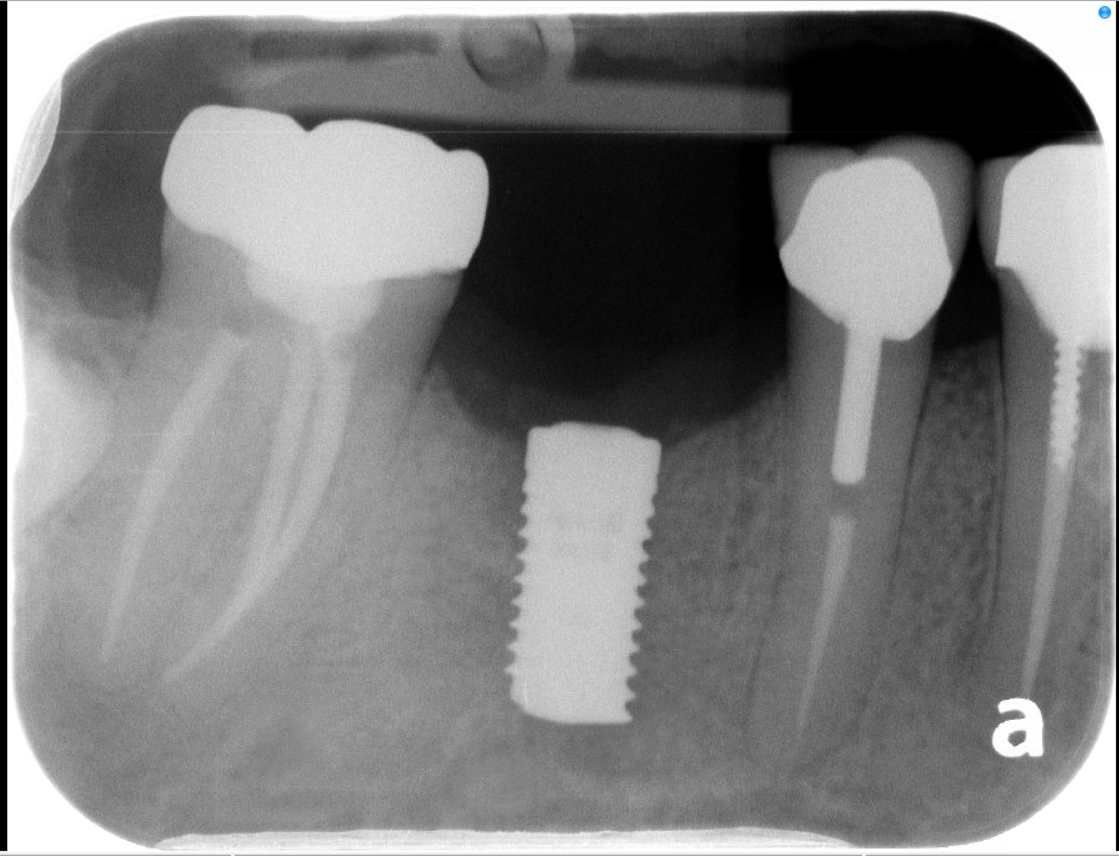

The most common application for an implant is replacing a single missing tooth. Unlike a bridge, an implant does not require the "grinding down" of healthy adjacent teeth.

• The Component: A medical-grade titanium post acts as a synthetic root.

• The Benefit: It prevents the surrounding teeth from shifting and stimulates the jawbone to prevent bone loss.

• The Result: Once healed, your general dentist places a custom crown that looks, feels, and functions like a natural tooth.

1. 3D Imaging & Planning: We use CT scans to evaluate bone density and plan the exact placement of each implant.

3. Integration (Osseointegration): We allow a healing period for the bone to fuse with the implant.